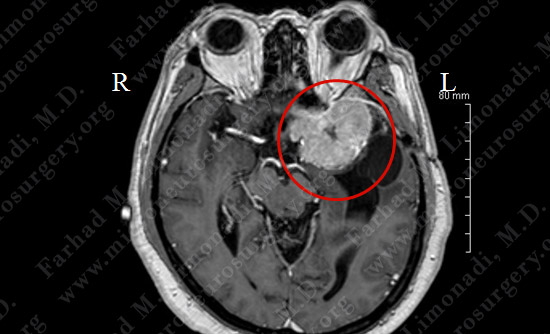

MRI scan of brain shows a left sphenoid wing meningioma arising from the dura (covering of brain) with intimate relationship with the optic nerve, middle cerebral artery, carotid artery. It is causing mass effect on the brainstem.

Vascular anatomy of the tumor was studies utilizing cerebral angiography. Tumor is outlined in red.